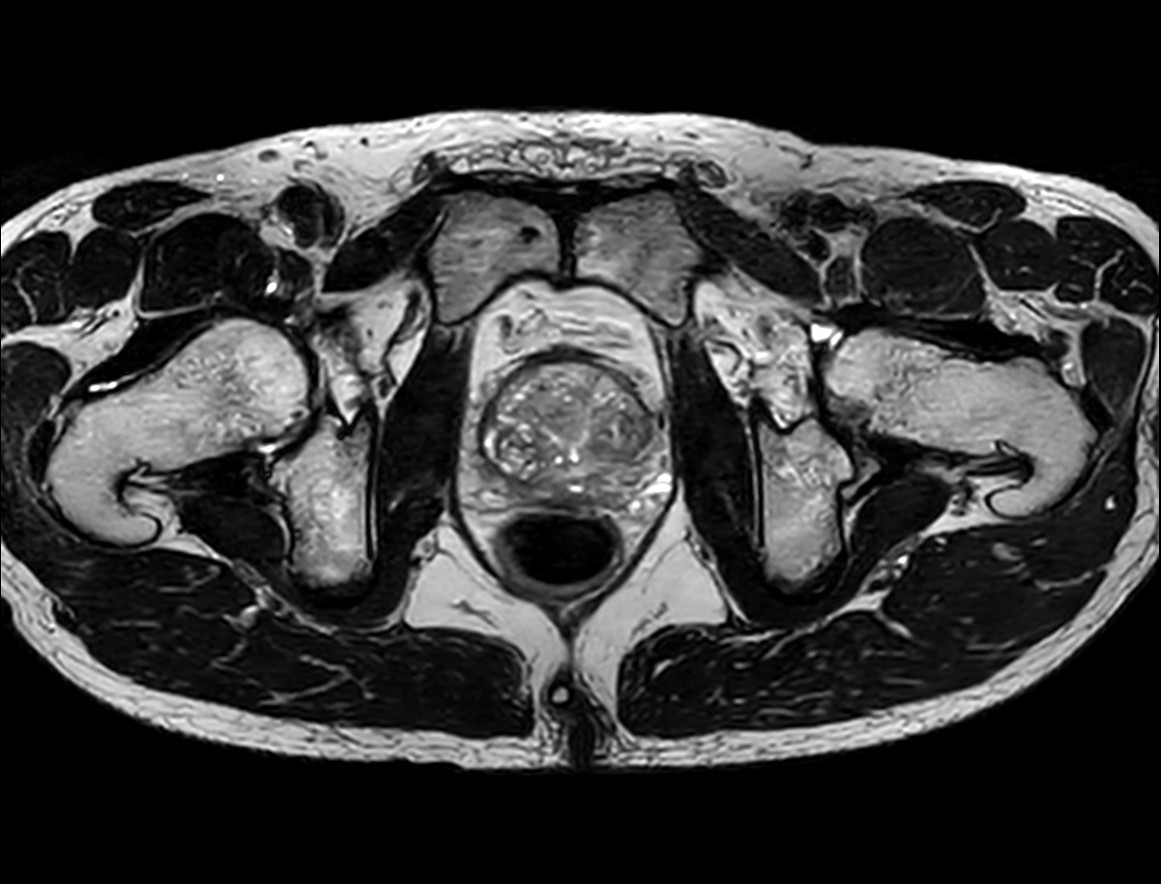

Fast Prostate imaging with SmartSpeed Precise

Kumamoto Chuo Hospital Japan